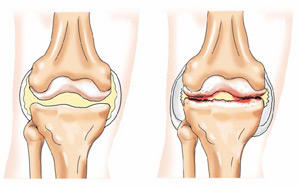

Артроз — это разрушение хрящевой ткани. Она истончается, расслаивается, в ней появляются трещины, в результате кость, находящаяся под хрящом обнажается, на ней появляются уплотнения, которые со временем разрастаются, превращаясь в шипы. Происходит деформация сустава. Человеку, страдающему артрозом коленного сустава, каждый шаг доставляет боль.

Можно сказать, что при этом заболевании суставной хрящ растрескивается, становится тоньше, теряя при этом свою волокнистость и амортизационные свойства, что, в принципе, не дает возможности во время движения смягчать периодические удары коленного сустава и тела.

Остеоартроз – это дегенеративное заболевание. Под нагрузкой, особенно если еще нарушен обмен веществ, изменяется питание хряща, покрывающего внутрисуставные поверхности костей. На хряще появляются трещины, он фрагментируется, разрушается, это сопровождается воспалением. Постепенно, если не лечиться, участки подлежащей кости теряют хрящевой покров, что приводит к механическому раздражению костной ткани, ее уплотнению, появлению костных разрастаний – остеофитов. Все это человек ощущает как боль, усиливающуюся при нагрузке на сустав, скованность, ограничение движений. Больному деформирующим остеоартрозом становится тяжело ходить, выполнять ежедневную работу. На рентгенограмме наблюдается неравномерное сужение суставной щели, кисты и остеофиты. Возможна и полная утрата суставного хряща, а соответственно, и обездвижение сустава. Стоит помнить, что остеоартроз – это не отложение солей, как принято говорить в народе, это разрушительный процесс, начинающийся с хрящевой ткани.